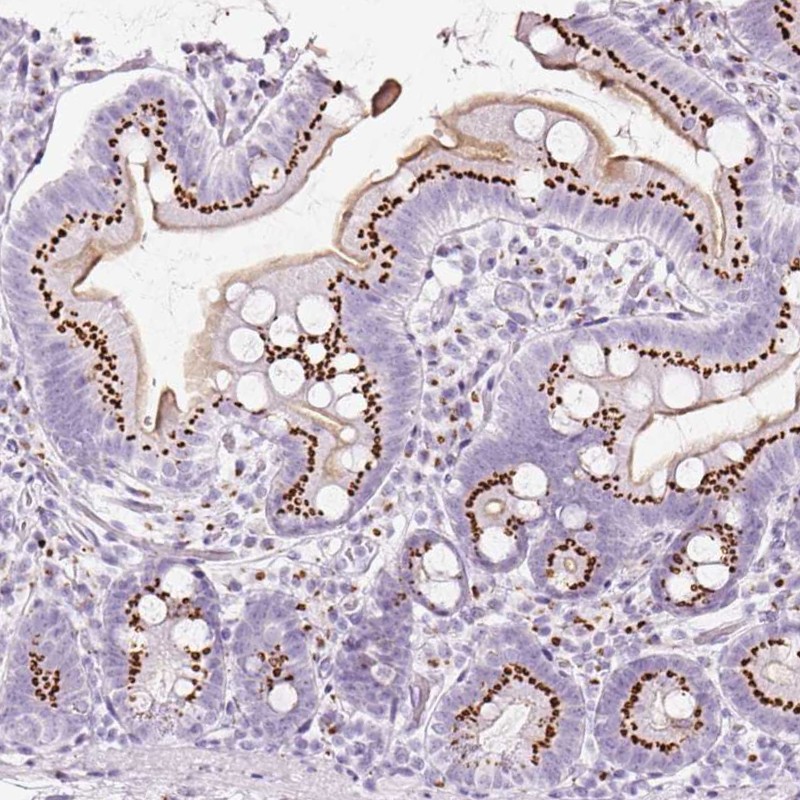

Immunohistochemistry analysis in human small intestine and pancreas tissues using Anti-SDF4 antibody. Corresponding SDF4 RNA-seq data are presented for the same tissues.